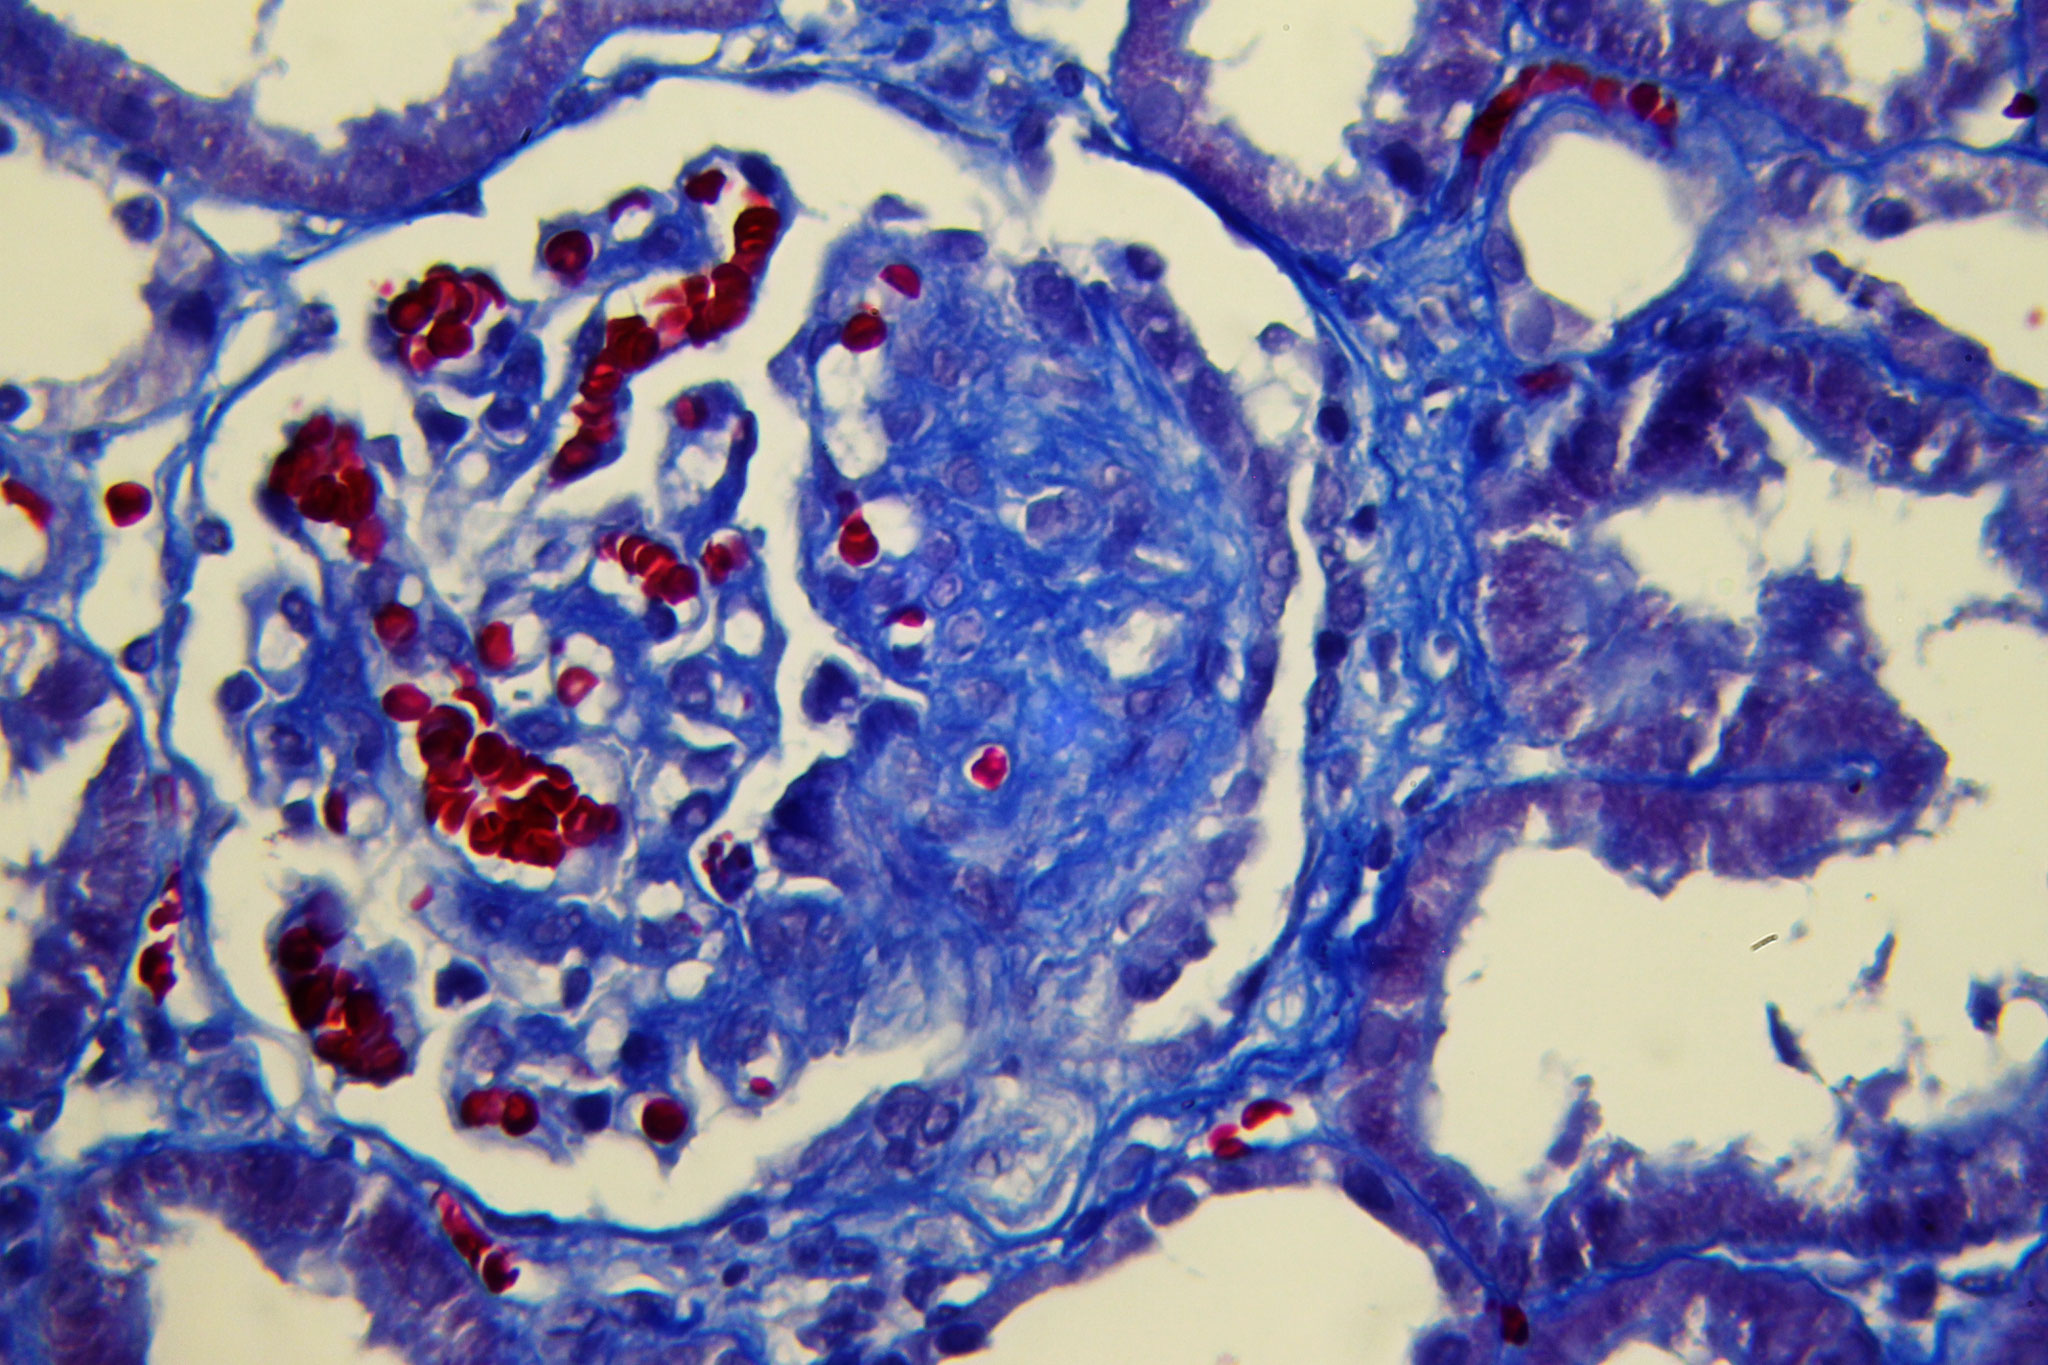

Patología Molecular

El diagnóstico sobre muestras de tejidos y líquidos corporales en plena era de la medicina del futuro, está basado en la integración de técnicas y conocimientos diferentes.

Hoy más que nunca es importante integrar una buena historia clínica con un correcto estudio de imagen y una buena morfología que además puede estar apoyada con proceso especiales complementarios relacionados con la Inmunología, Biología Molecular y Citogenética, generando así un estudio integral conocido como Patología Molecular.